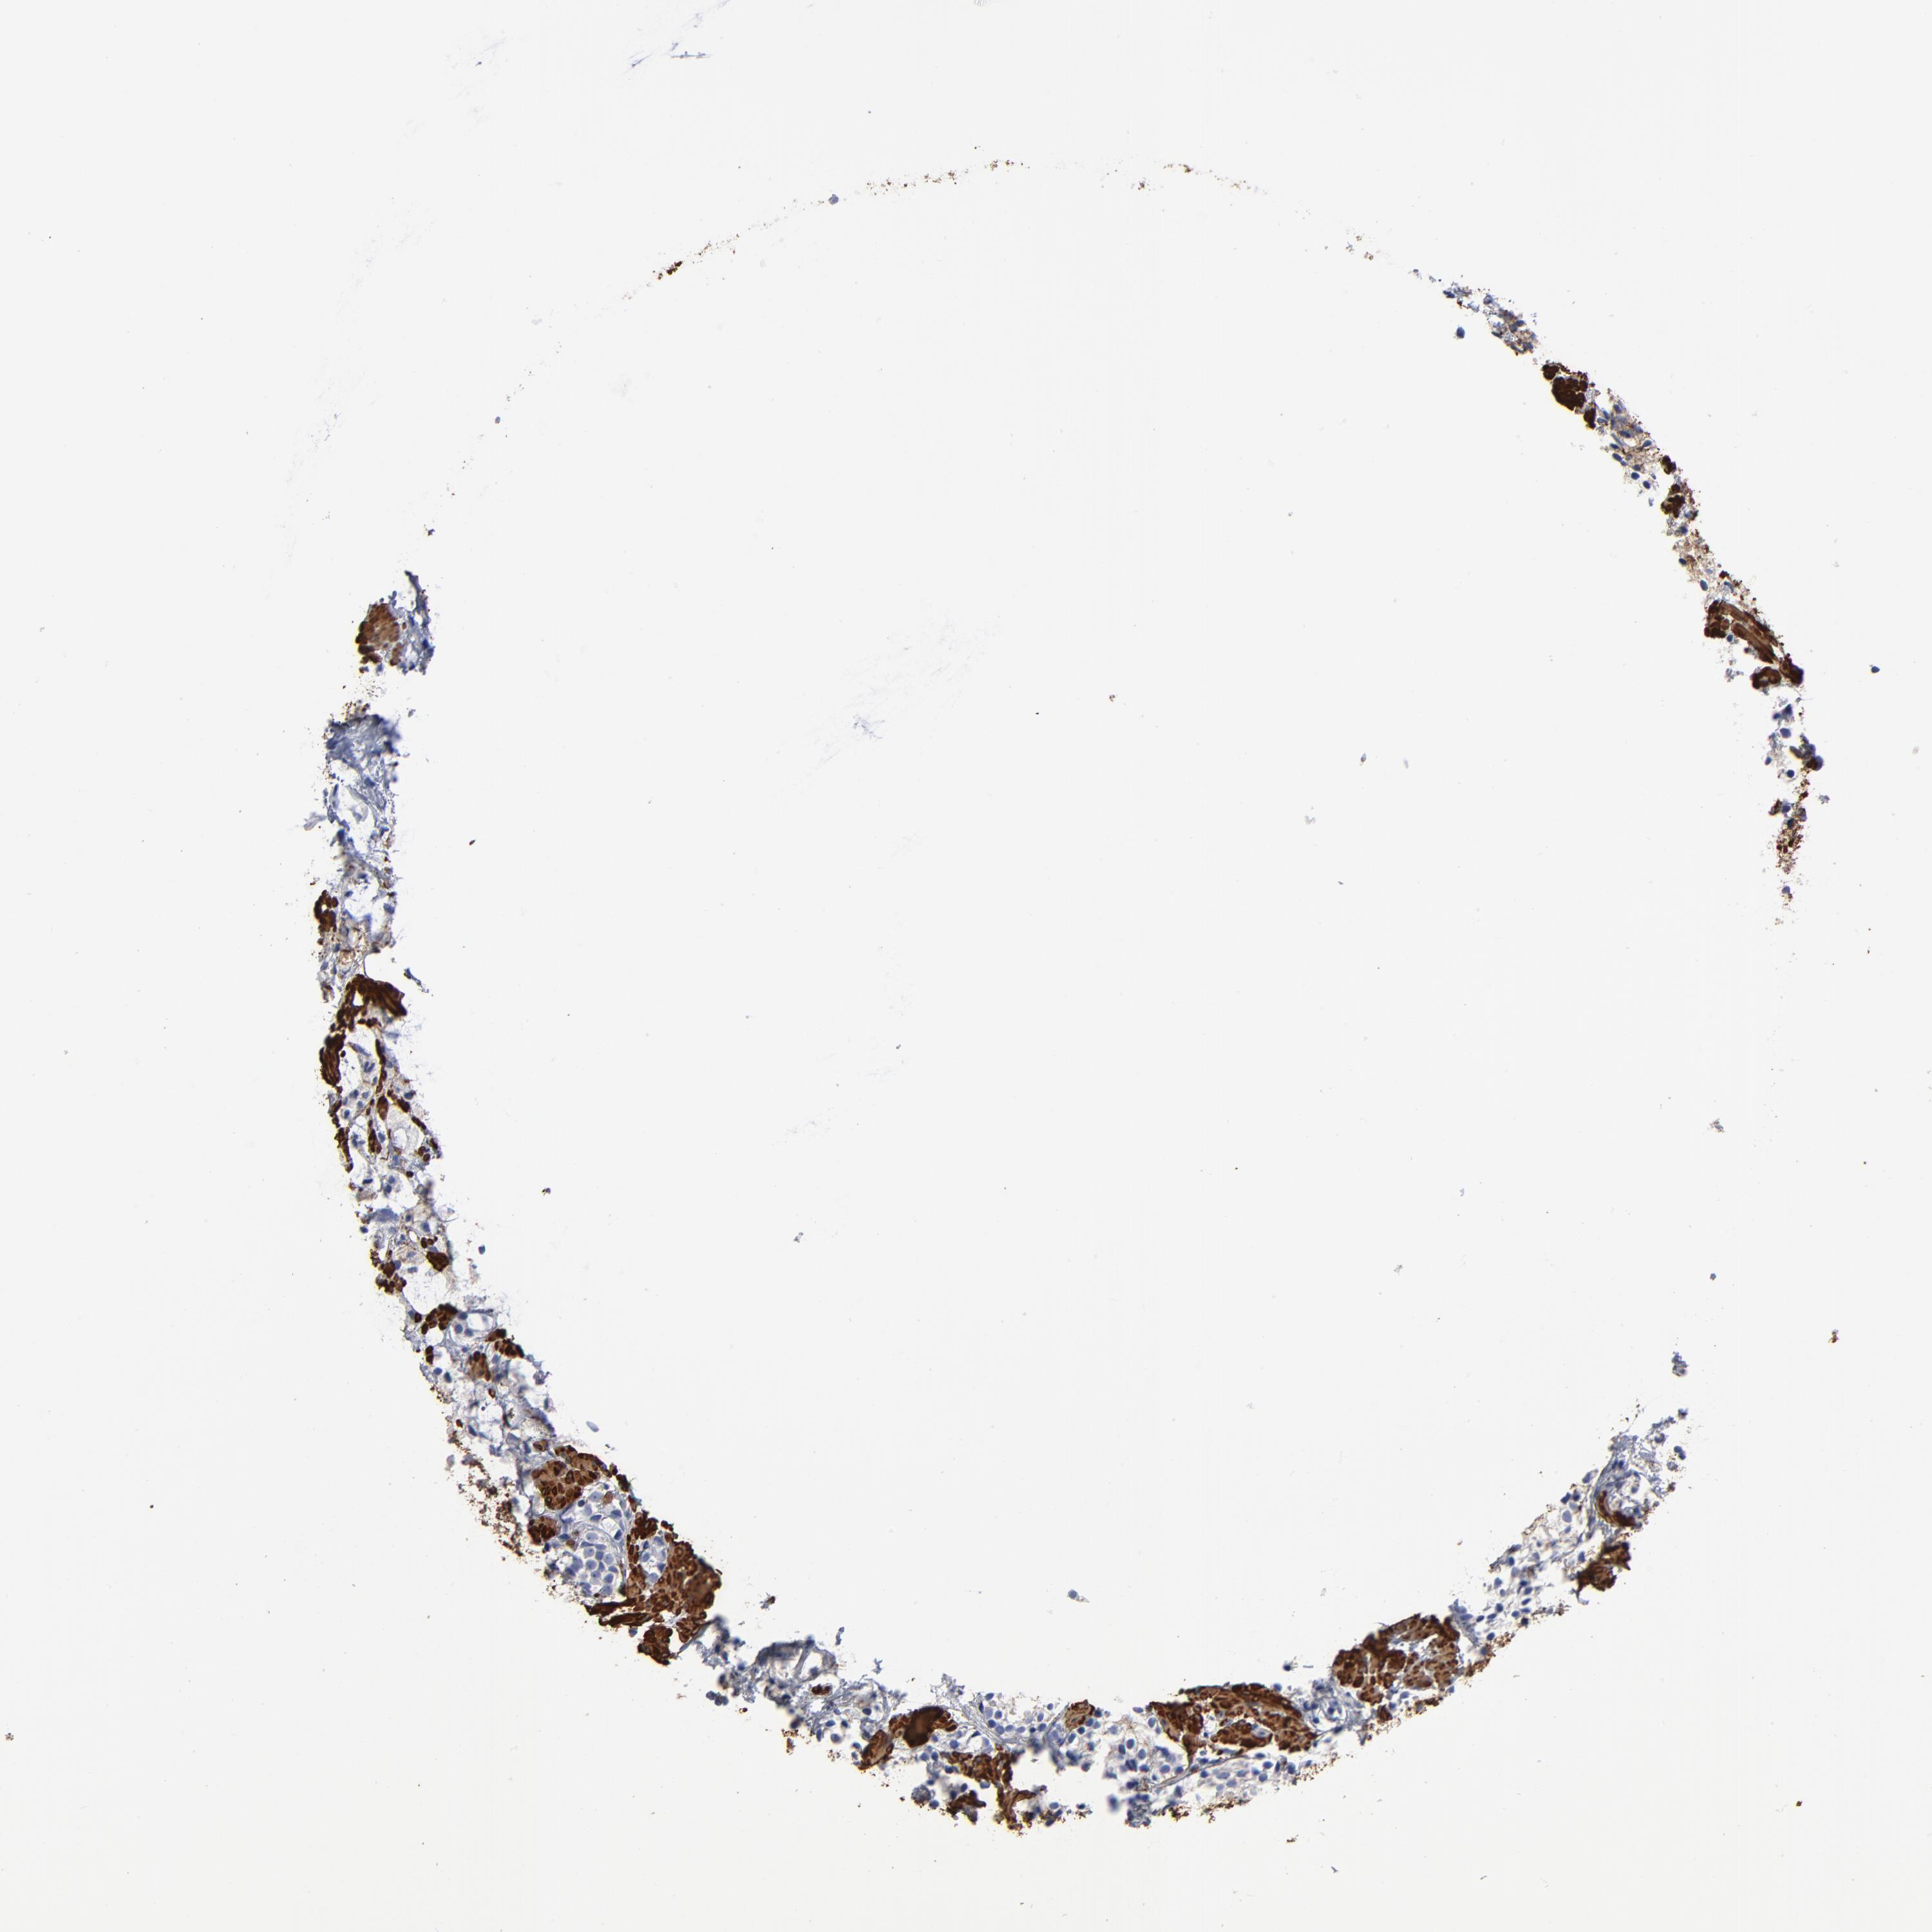

PROSTATE CANCER - Protein expressioni

A mouse-over function shows sample information and annotation data. Click on an image to view it in a full screen mode. Samples can be filtered based on level of antibody staining by selecting one or several of the following categories: high, medium, low and not detected. The assay and annotation is described here.

Note that samples used for immunohistochemistry by the Human Protein Atlas do not correspond to samples in the TCGA dataset.

Antibody stainingi

Antibody staining in the annotated cell types in the current human tissue is reported as not detected, low, medium, or high, based on conventional immunohistochemistry profiling in selected tissues. This score is based on the combination of the staining intensity and fraction of stained cells.

Each image is clickable and will lead to virtual microscopy that enables deeper exploration of all samples and also displays staining intensity scores, fraction scores and subcellular localization as well as patient and tissue information for each sample.

HPA041264

HPA041271

CAB000002

CAB003761

CAB013531

Staining

High

Medium

Low

Not detected

Intensity

Strong

Moderate

Weak

Negative

Quantity

>75%

75%-25%

<25%

None

Location

Nuclear

Cytoplasmic/membranous

Cytoplasmic/membranous,nuclear

Adenocarcinoma, NOS

Adenocarcinoma, High grade

Adenocarcinoma, Low grade

Adenocarcinoma, Medium grade